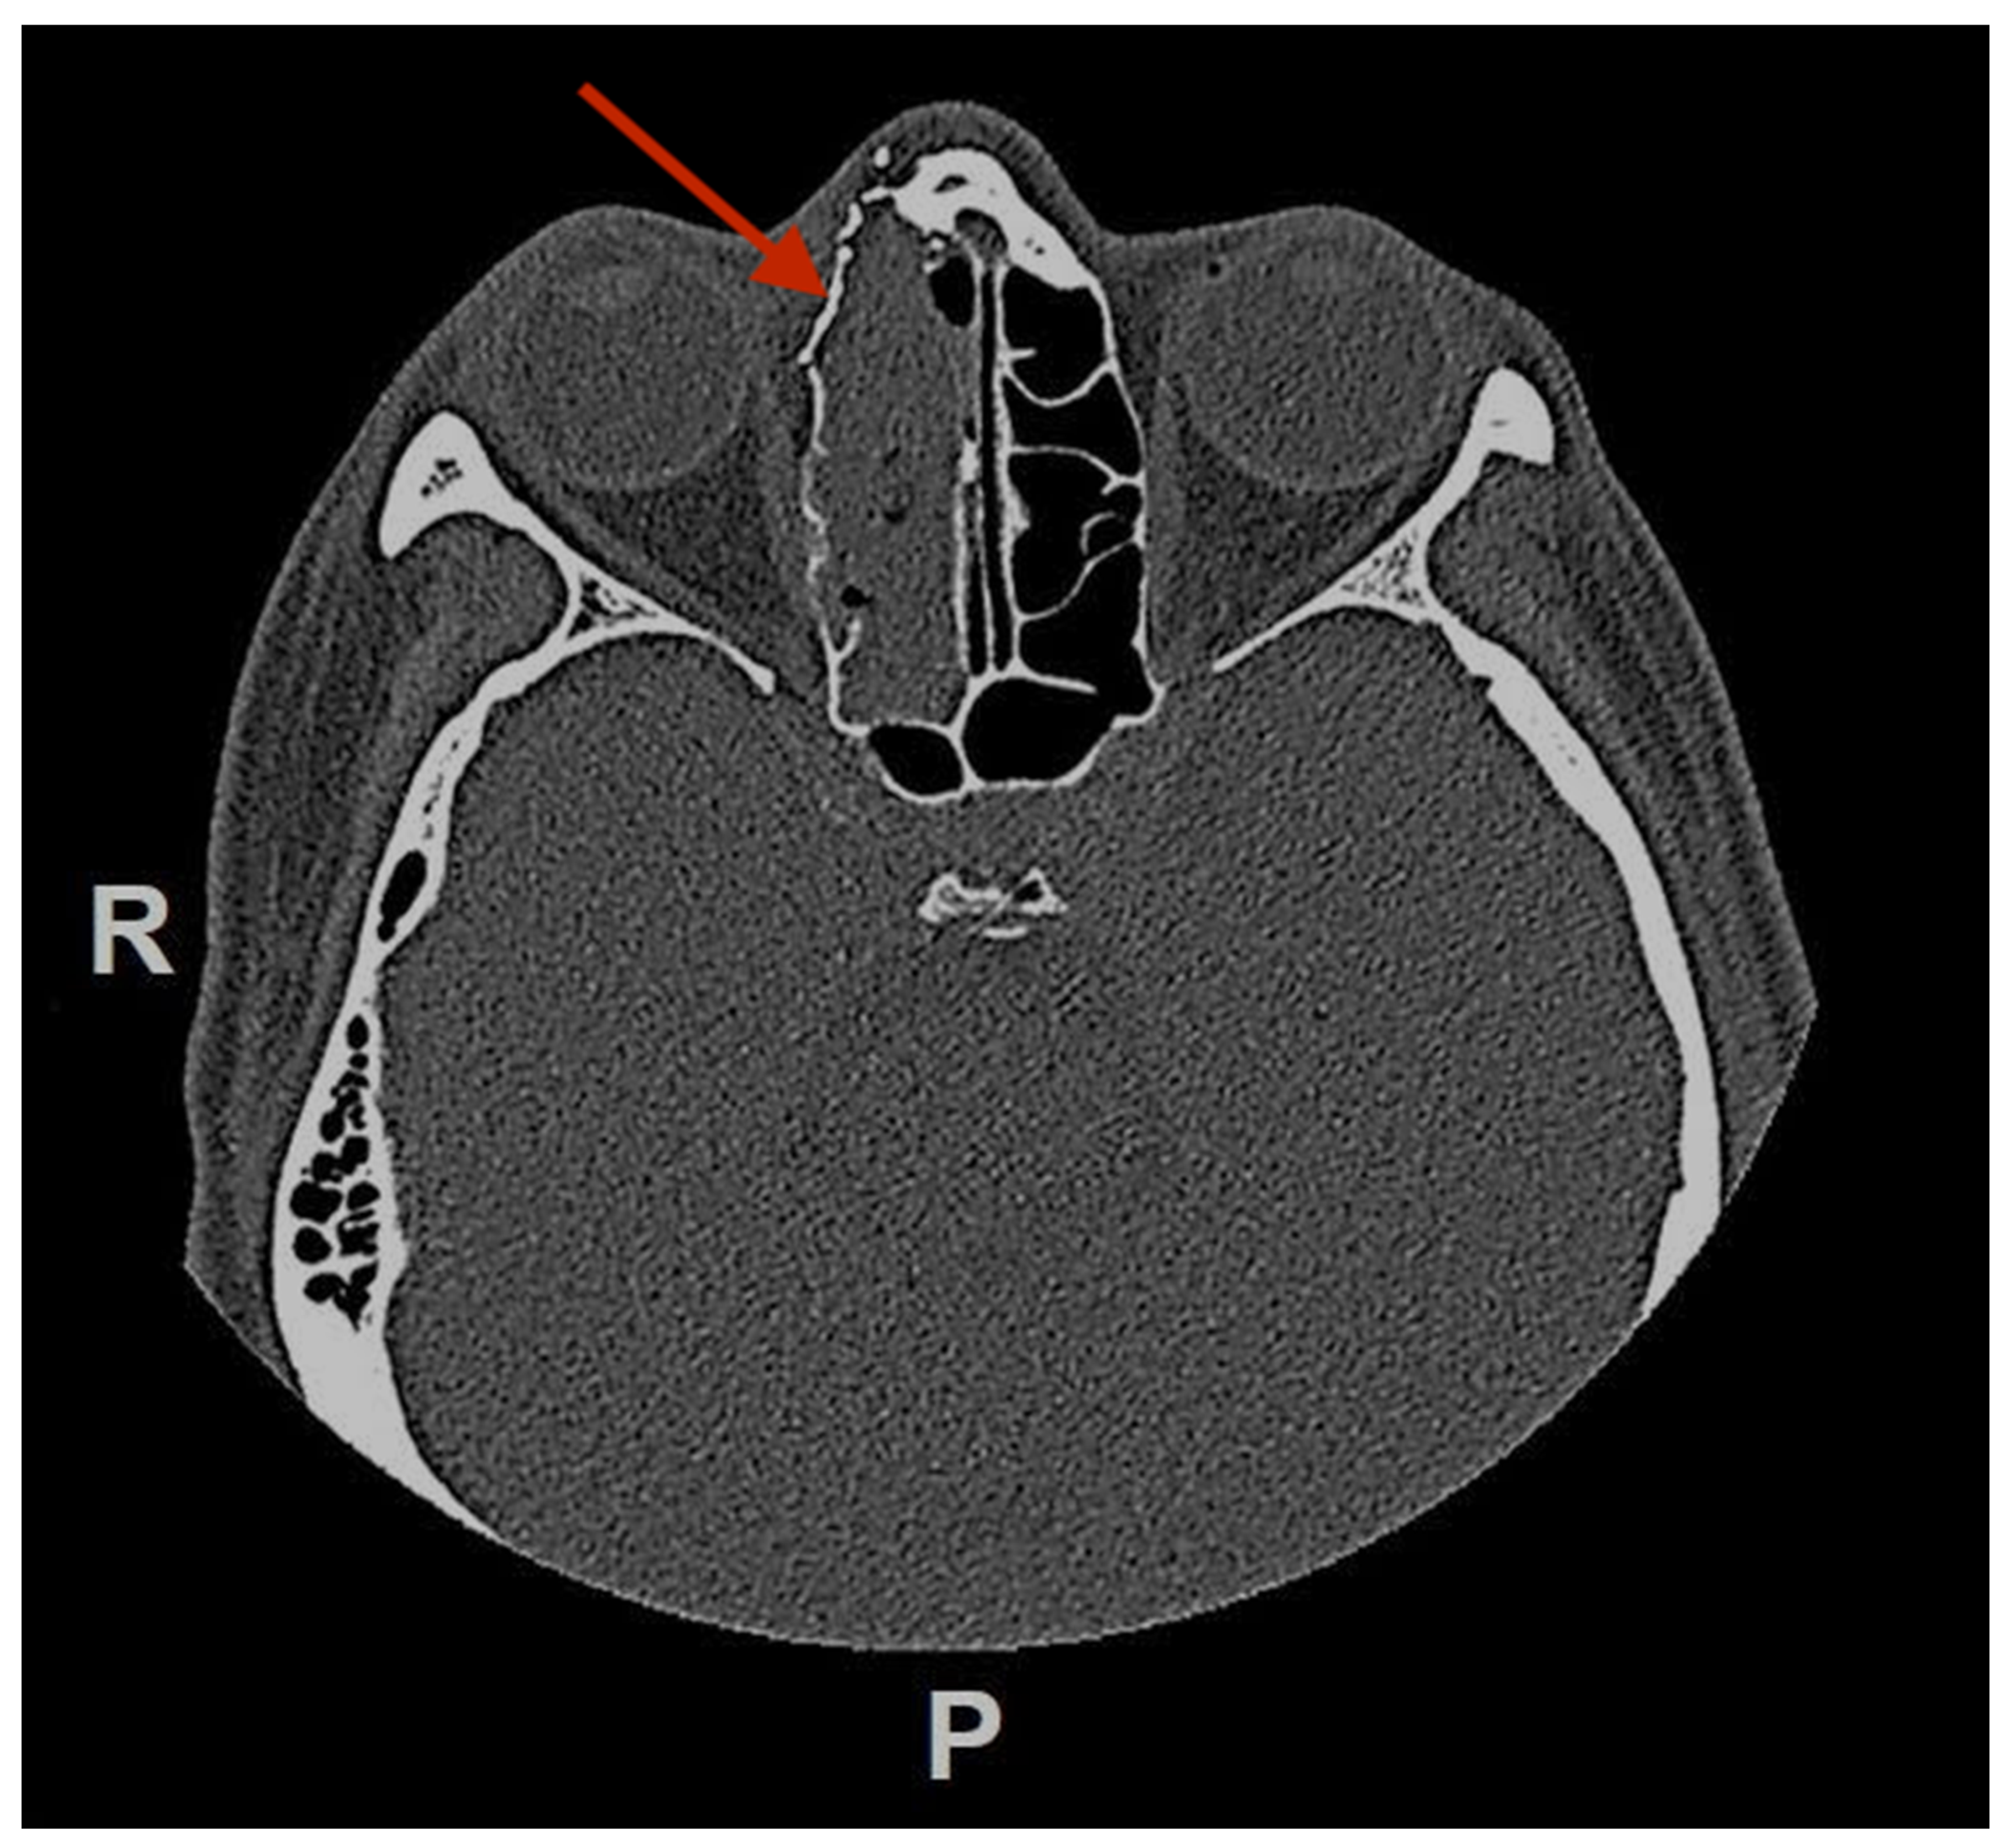

Figure 6.

Postoperative (3 weeks) CT-scan in axial view showing the reconstruction of the medial right orbit wall with a titanium mesh. (red arrow pointing at the titanium mesh). R = right, P = posterior.